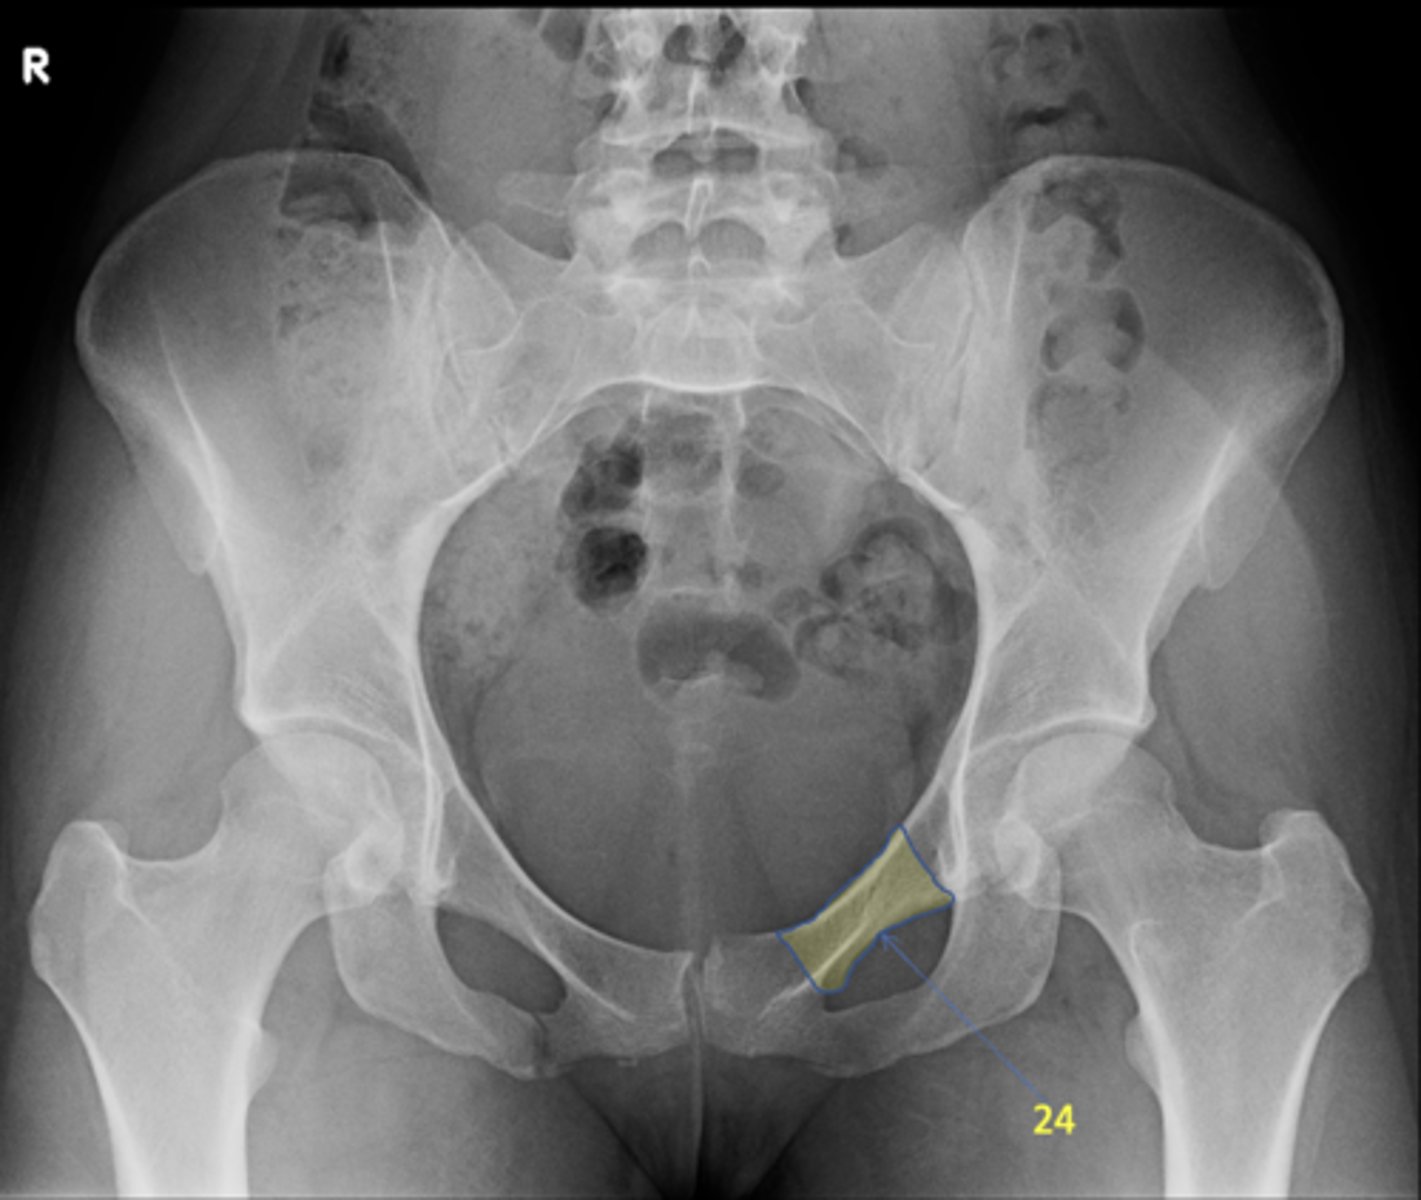

21

Left superior pubic ramus

<p>ID 24</p>